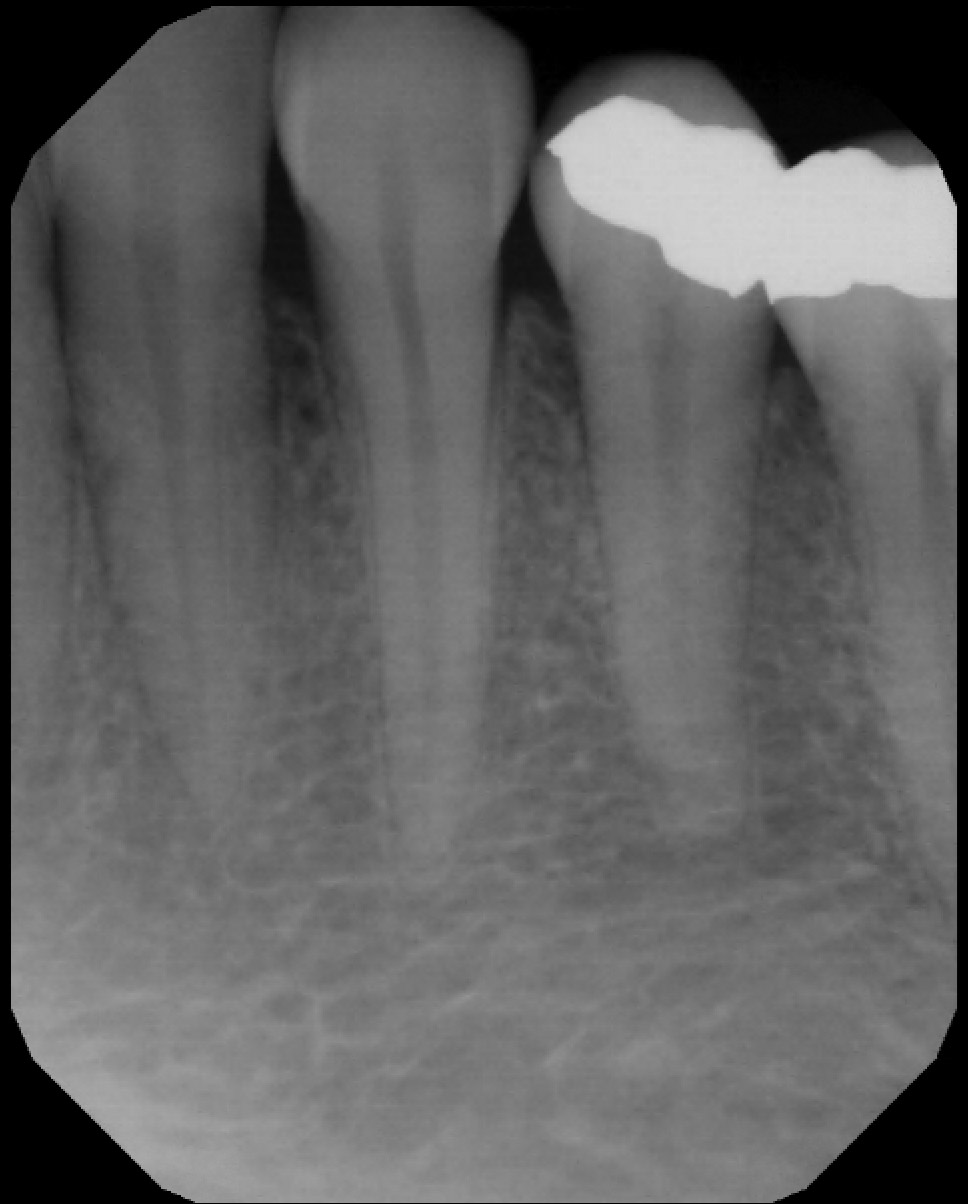

IX. RADIOGRAPHS

Note: 11 (US # 8) and 21 (US # 9) have caries into the pulp and peri apical lesions

X. RADIOGRAPHIC FINDINGS

• Caries: 13 M (D) (US # 6), 12 D (D) (US # 7), 11 M (D) (US # 8), 21 M/D (D) (US # 9), 42 M (E) (US # 26), 43 M (E) (US # 27)

• Residual roots: 45 (US # 29). Fractured: 44 (US # 28).

• Endodontic fillings: 15, 14, 44, 45, 47* (US # 4, 5, 28, 29 and 31*)

• Periapical lesion on 11 (US # 8) and 21 (US # 9): correlates with the clinical finding of eroded teeth down to the dentin (almost the dentino-pulp junction)

• Note : The root canal on tooth 47 (US # 31) was done in Algeria and seems to have been an attempt. There is a broken instrument in one of the canals.

• Conclusion: The radiolucencies seen at the apex of 11 and 21 (US # 8 and 9) were not periapical lesions. I retook a PA with a different angle (see next slide)

• Additional radiographs

Note: No periapical lesion is noted on 11 and 21 (US # 8 and 9).